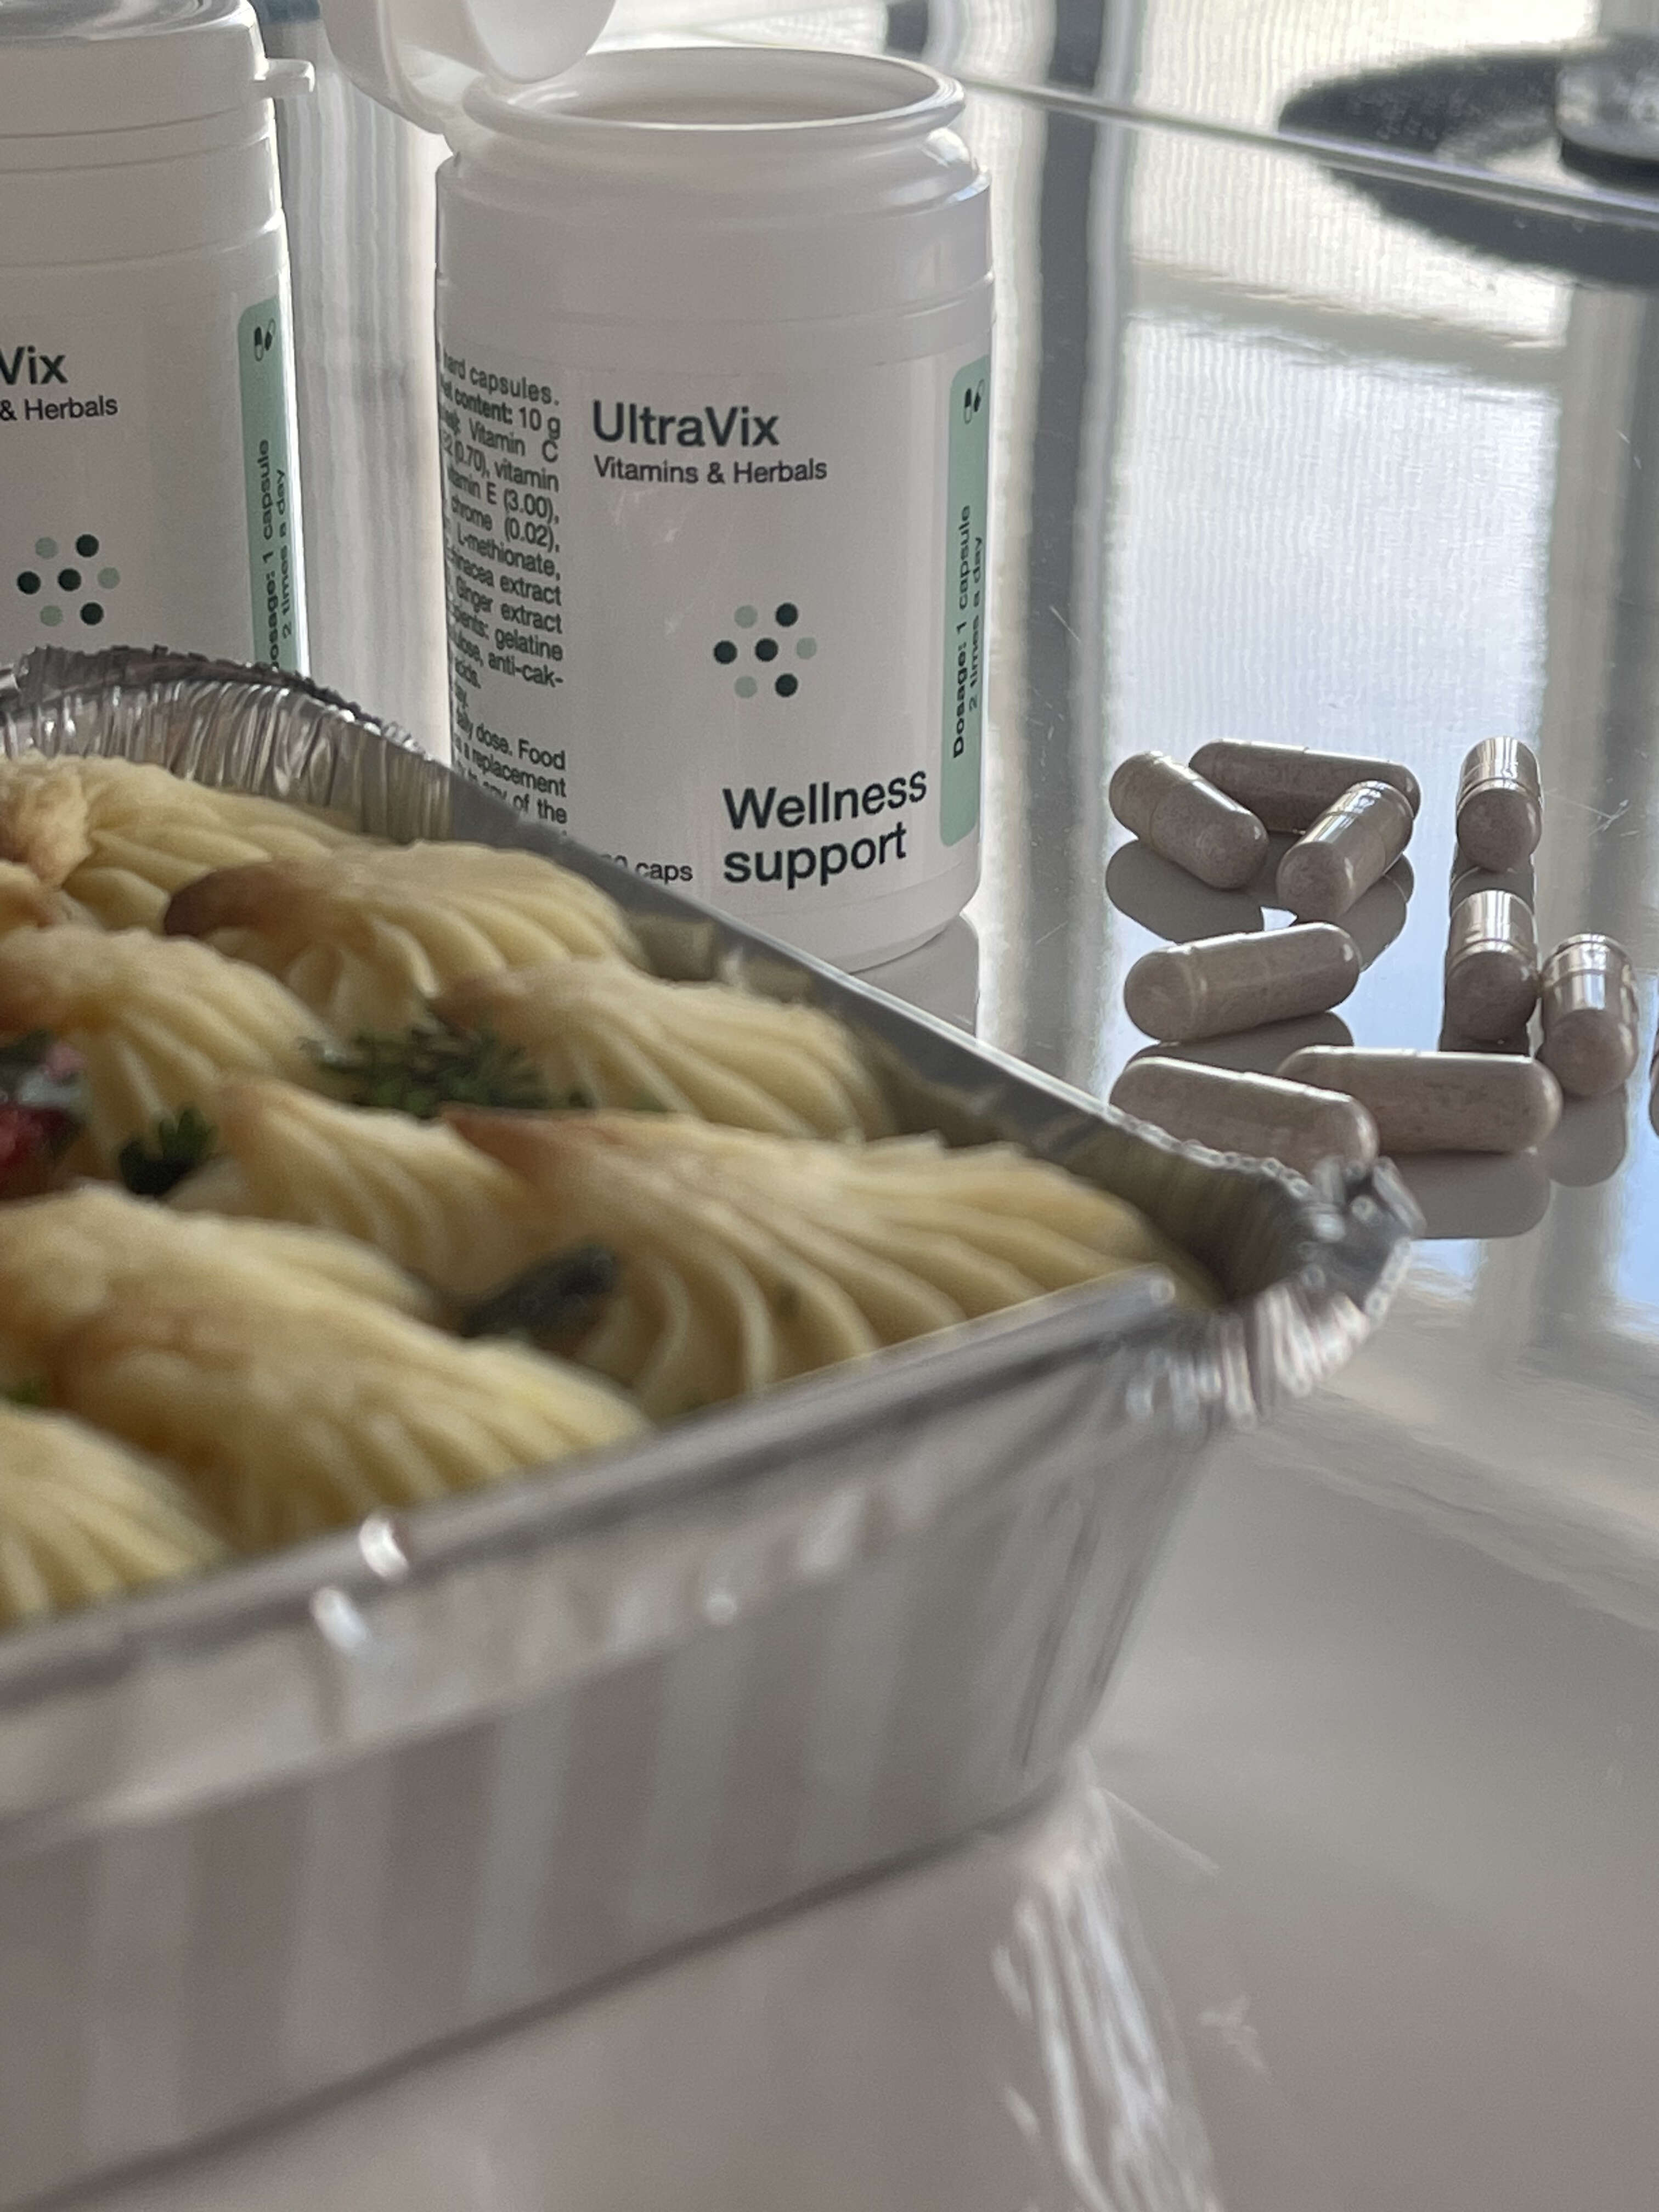

Миналата година нов продукт „UltraVix“, разработен от учените от институт по гастроентерология, който създава оптимален баланс на чревната микробиота и на целия храносмилателен тракт, премина всички клинични тестове и сертификация.

Това е билков комплекс, който при консумация стимулира синтеза на 4 милиарда единици, формиращи колонии (CFU/g), помага за поддържане на баланса на чревната микробиота и оказва уникално въздействие върху организма.

Това е мощен билков комплекс, който съчетава съвременна медицинска технология с естествената сила на билковите лекове като черния кимион.

Продуктът е формулиран с внимателно проучени растителни екстракти, а капсулната форма гарантира незабавна абсорбция.

Съставът на продукта е напълно натурален и абсолютно безопасен, което е важно за хора с хронични заболявания. UltraVix не предизвиква странични ефекти и може да се приема без надзор от специалист.